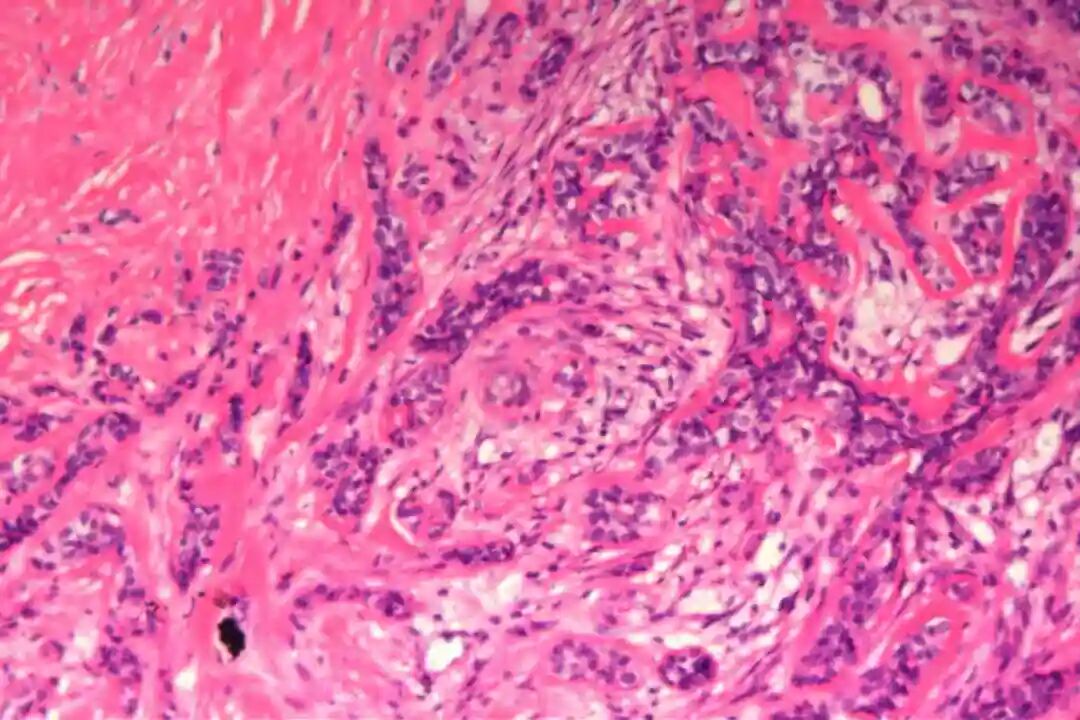

细胞形态:基底样肌上皮细胞体积较小,呈圆形或卵圆形,细胞核深染、染色质均匀,核仁不明显,胞质稀少、淡嗜酸性;腺上皮细胞体积略大,呈柱状或立方状,细胞核淡染、染色质疏松,核仁清晰,胞质丰富、嗜酸性。实性巢团内可见少量微小腔隙,腔隙内可含有少量嗜酸性或嗜碱性黏液样物质(PAS染色阳性),这是实体型与其他实性肿瘤的重要鉴别点;核分裂象少见,一般≤5个/10HPF,部分实体型区域可出现轻度至中度细胞异型性,但无明显恶性增殖活性表现,与高级别乳腺癌的细胞异型性有明显区别。

实体型区域与经典型区域无明显明确界限,相互穿插分布,实体型巢团可逐渐过渡为经典型的筛状或管状结构,两种区域的细胞成分相互延续,均可见腺上皮细胞与肌上皮细胞的混合存在,无明显细胞异型性差异(实体型区域异型性略高于经典型,但整体温和)。这种混合性形态是本病的重要镜下特点,也是与单纯实体型PACC、单纯经典型PACC的主要区别。